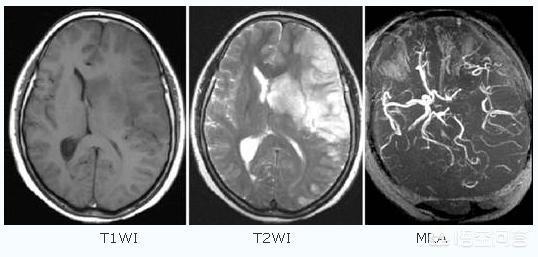

脳梗塞とは何か?脳梗塞とは、血液中のさまざまな塞栓物(心臓の壁に付着した血栓、動脈硬化のプラーク、脂肪、腫瘍細胞、線維軟骨、空気など)が血流に乗って脳動脈に入り、血管を閉塞し、動脈から栄養を受けている部分の脳組織が虚血壊死を起こす病気です。

簡単に言えば、脳の血管が詰まって脳虚血を起こしたときに起こる脳細胞の壊死である。

脳梗塞は、臨床的には虚血性脳卒中とも呼ばれ、アテローム性動脈硬化症、高血圧、糖尿病、冠動脈性心疾患など様々な原因によって脳の血管に血液が供給されなくなり、虚血、低酸素症、局所脳組織の壊死を引き起こす!

脳卒中は出血性脳卒中と虚血性脳卒中に分けられる。虚血性脳卒中(脳梗塞)は中国で最も多い脳卒中である。虚血性脳卒中とは、血管の閉塞により脳への血流が不足し、脳組織が虚血性壊死を起こし機能を失う病態であり、脳塞栓症や脳血栓症が代表的な原因である。虚血性脳梗塞の発症前には、突然片側の手足のしびれや脱力感、言語障害、目のかすみ、平衡感覚障害などの一時的な脳虚血症状(一般にミニ脳梗塞と呼ばれる)が出現することがあり、この症状は短期間出現し、すぐに回復します。脳卒中の重要な前兆です。..脳頸動脈の動脈硬化性プラークと狭窄は虚血性脳卒中を引き起こす重要な因子である。中高年に加え、高血圧、高コレステロール、糖尿病、長期喫煙者が最も多い。

虚血性脳卒中は、血管の血液供給部位の低酸素性壊死によって引き起こされる脳疾患の症状である。一般的な発症機序である:

- 脳血栓症:(1)血液の粘度の増加による血栓の形成。(2)脳の動脈に脂肪が蓄積してプラークを形成し、脳の血管の狭窄を悪化させることによる血流障害。

- 脳塞栓症血栓、脂肪、気泡など、脳以外の部位からの障害物が循環系を介して脳血管に入り込み、局所的に脳血流障害を引き起こす。